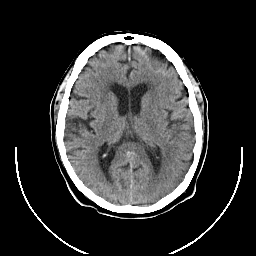

CT Study #1 -- Slice #15